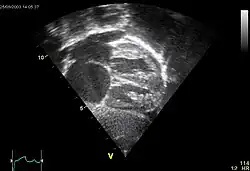

Echocardiography

In transthoracic echocardiography, an atrial septal defect may be seen on color flow imaging as a jet of blood from the left atrium to the right atrium.

If agitated saline is injected into a peripheral vein during echocardiography, small air bubbles can be seen on echocardiographic imaging. Bubbles traveling across an ASD may be seen either at rest or during a cough. (Bubbles only flow from right atrium to left atrium if the right atrial pressure is greater than left atrial). Because better visualization of the atria is achieved with transesophageal echocardiography, this test may be performed in individuals with a suspected ASD which is not visualized on transthoracic imaging. Newer techniques to visualize these defects involve intracardiac imaging with special catheters typically placed in the venous system and advanced to the level of the heart. This type of imaging is becoming more common and involves only mild sedation for the patient typically.

If the individual has adequate echocardiographic windows, use of the echocardiogram to measure the cardiac output of the left ventricle and the right ventricle independently is possible. In this way, the shunt fraction can be estimated using echocardiography.

- 1 2 3 "UOTW #54 - Ultrasound of the Week". Ultrasound of the Week. 30 July 2015. Archived from the original on 9 May 2017. Retrieved 27 May 2017.